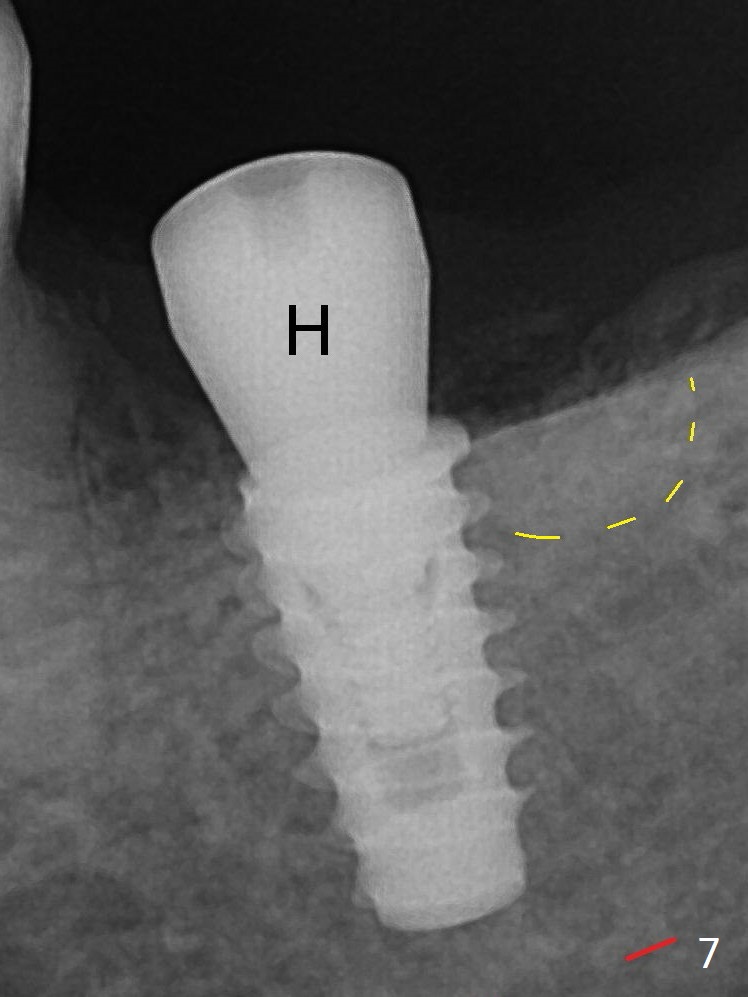

After Marking Bur and 4.3 mm Magic Drill, a 5x9 mm IBS implant is placed with 2.8 mm clearance from the Inferior Alveolar Canal (Fig.6). Following deepening the osteotomy with Final Drill, the implant is placed deeper (Fig.7). The osteotomy happens to be established in the mesial socket, since the distal socket has not completely healed (Fig.6 yellow dashed line). Granulation tissue is removed. Since the lingual crest is lower than the buccal one (Fig.1 B), there is lingual thread exposure after implant placement (Fig.5). The exposed thread is covered by bone graft (autogenous bone, allograft and Osteogen, Fig.5 pink circles). Some of the graft is apparently pushed into the distal socket (Fig.7 yellow dashed line) post GBR and suture. As the implant is placed twice, insertion torque is <10 Ncm (although the implant is stable). A 5x3 mm healing abutment is placed (Fig.7 H). There is no apparent bone loss 4 months postop (Fig.10).